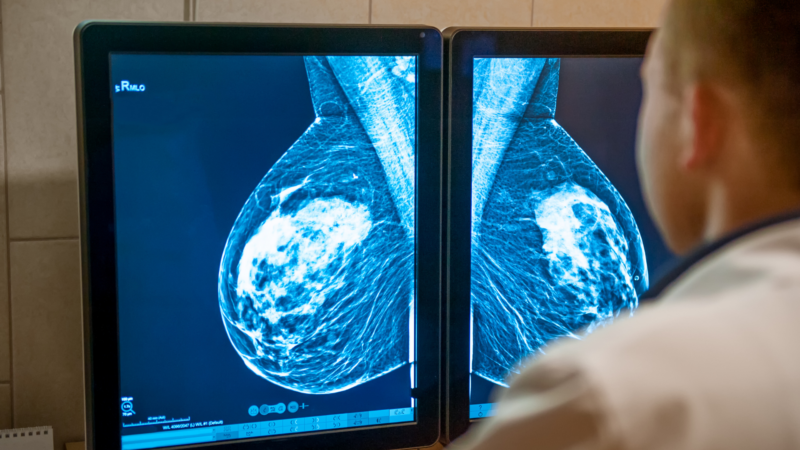

University Hospitals Sussex is one of 15 trusts across the country that participated in a project that looked at the effectiveness of using an AI system to analyse mammograms – an X-ray of the breast to help detect cancers – to see if it could improve the early detection of breast cancer by seeing tiny signs of cancer that can be missed at this stage.

After the scan is taken, the mammogram is typically reviewed by two highly skilled radiologists or film readers, who look for any signs of cancer. Upon review, they then decide if the scan is ‘normal’ without signs of cancer or if further investigation is needed.

Over the course of the two-month project, more than 12,000 mammograms considered as ‘normal’ were reviewed using the AI system which acts as an extra ‘reader’ alongside radiologists, to flag any scans it thinks needs to be looked at again.

The AI system suggested that just under 10% of those mammograms should be re-read by a clinical panel to identify any potential cancers that were not detected in the initial screening.